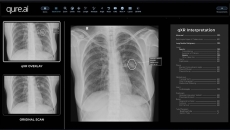

Qure.ai's qXR software will enable Mylab's upcoming x-ray device to quickly detect TB.

The model showed 86% sensitivity and a specificity of up to 96.1%.